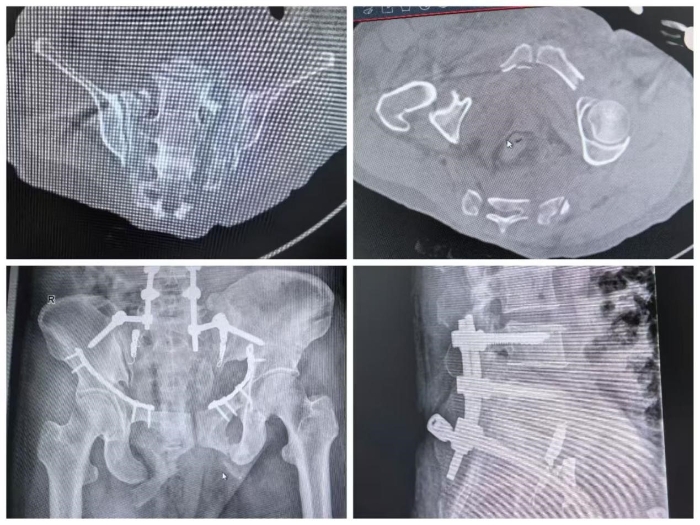

針對(duì)其Tile C型(垂直不穩(wěn)定)骨盆骨折,副院長(zhǎng)馬剛組織團(tuán)隊(duì)進(jìn)行了深入的術(shù)前討論。為爭(zhēng)取最佳功能預(yù)后,需盡早施行手術(shù),實(shí)現(xiàn)解剖復(fù)位與堅(jiān)固固定。團(tuán)隊(duì)制定了周密方案——以后路腰髂螺釘固定糾正骶骨垂直移位,并采用改良Stoppa前路入路,單一切口完成雙側(cè)恥骨上下支骨折的切開(kāi)復(fù)位內(nèi)固定,最大程度減少手術(shù)創(chuàng)傷。

8月5日,馬剛帶領(lǐng)團(tuán)隊(duì)成功為患者進(jìn)行了“骨盆骨折切開(kāi)復(fù)位后路腰髂螺釘固定+前路改良Stoppa入路鋼板內(nèi)固定術(shù)”。術(shù)后影像顯示骶骨垂直移位完全糾正,骨折對(duì)位及內(nèi)固定位置極佳,手術(shù)獲得圓滿(mǎn)成功。經(jīng)過(guò)后續(xù)系統(tǒng)康復(fù),患者恢復(fù)良好,順利出院。